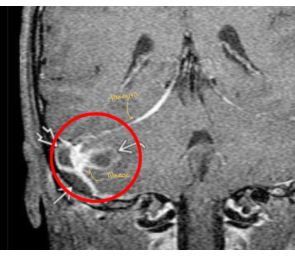

Para que sirve la RM en mastoiditis y específicamente en T2

A

Hiperseñal, disminución de señal es senos sigmpideos y captación de contraste

Q

De que enfermedad se trata y qué complicacion está presentando

Mastoiditis con invasión a SNC con un absceso que provoca una meningitis